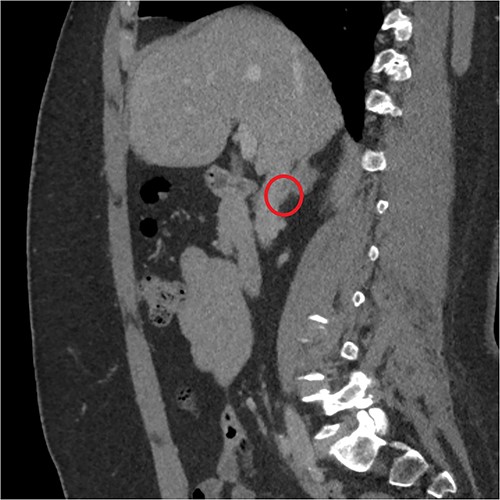

The endocrinological study showed a hypersecretion of cortisol with suppressed ACTH (550 mcg/l, ACTH 1.1 ng/ml, urinary free cortisol 255 mcg/24 h, positive overnight Nugent test). The serum concentration of renin and aldosterone and the urinary concentration of metanephrine are instead normal. Therefore, the patient underwent an abdominal CT scan that showed a right adrenal lesion of about 7 cm with an adenomatous appearance (Fig. 1). The saggital 3D reconstruction of CT scan in venous phase had raised the suspicion of short course of the adrenal vein in the lower lateral lip of the mass (Fig. 2). To better define the relationship between the neoplasm and the inferior vena cava, the vascularization of the adrenal gland with any anatomical anomalies and the specific location of the middle adrenal vein, a 3D printed model was created in 1:1 size based on the preoperative CT scan.

(a) and (b) The abdominal CT scan showed a large right adrenal tumor.

Sagittal 3D reconstruction of CT scan in venous phase. In particular, the images had raised the suspicion of the short course of the adrenal vein in the lower lateral lip of the mass.